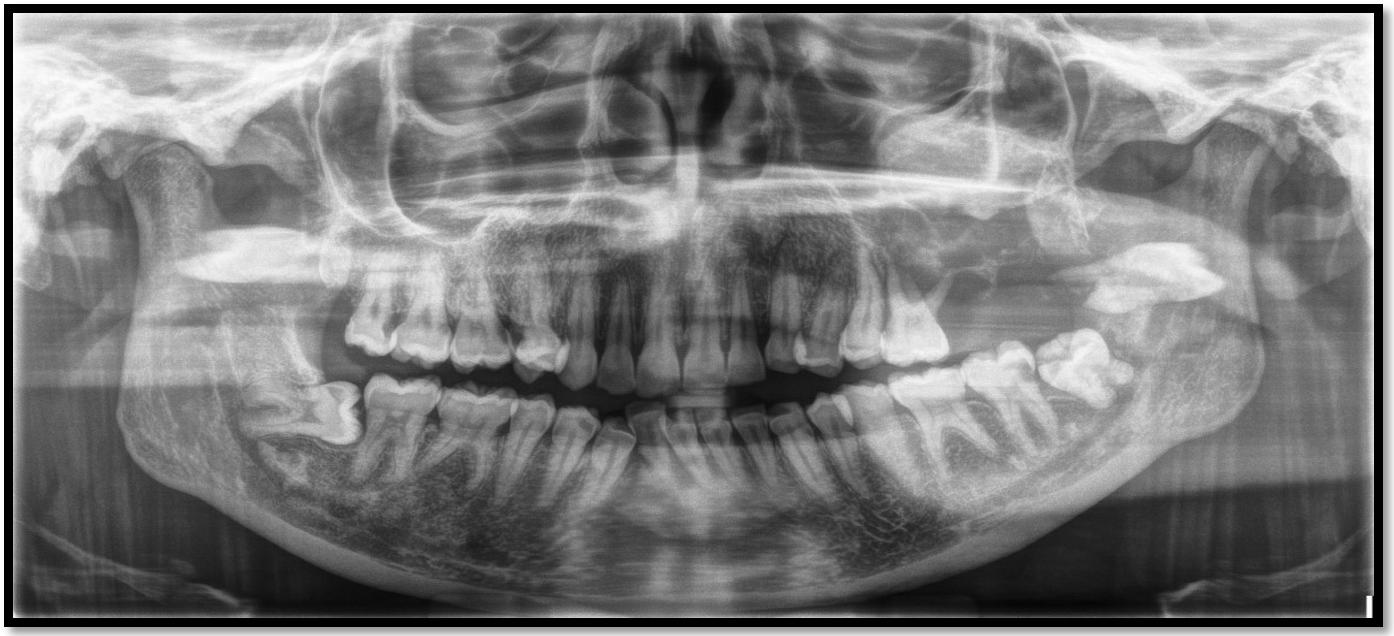

8.OdontogenicMyxoma:CaseReport (Pg.77-86)

MyxomaOdontogénica:ReportedeCaso

EvaChiang,DDS,MPH,LynnSolomon,DDS,MS,ElíasMorón,DDS,MPH,MHL